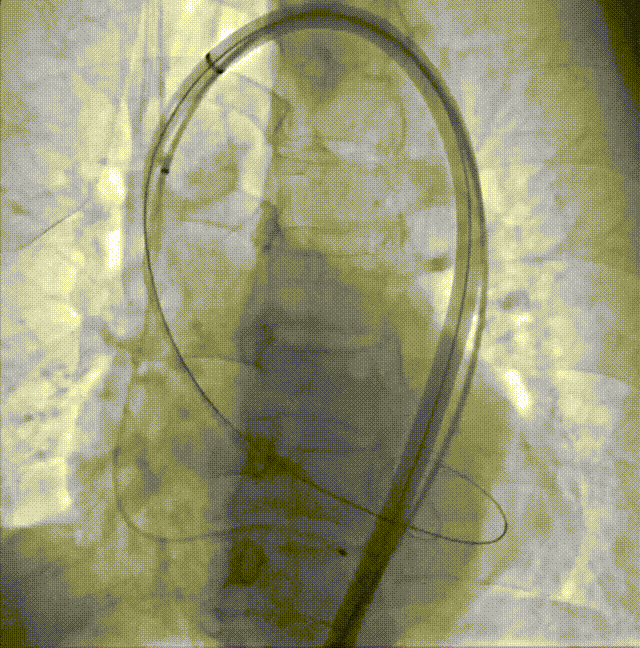

导引鞘定位STJ